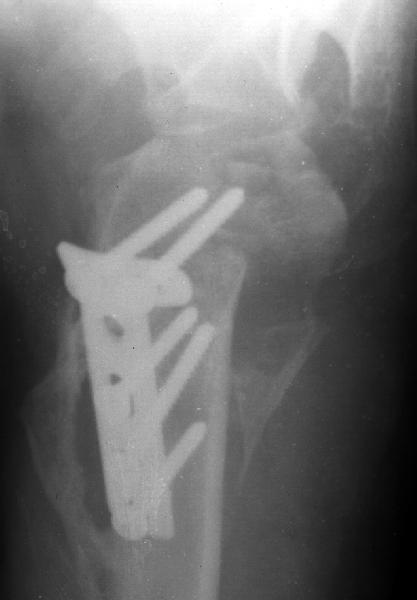

Мужчина 25 лет 16 августа 2002 г. в автоаварии получил перелом шейки плеча (снимок 1); 5 сентября в городской больнице выполнен остеосинтез пластинкой (снимок 2).К настоящему времени попал к нам на разработку ввиду выраженной контрактуры плечевого сустава. В течение последнего месяца беспокоят умеренные боли в области плечевого сустава, усиливающиеся при разработке, еще и торчит край пластинки. Нынешняя рентгенологическаякартина на снимках 3 и 4. Головка плеча уменьшается, сращение сомнительное.Кроме удаления пластинки, что еще на сегодня целесообразно сделать?Заранее спасибо.